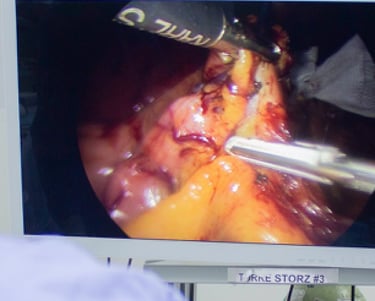

El bypass gástrico ofrece una pérdida de peso significativa y sostenida a largo plazo, además resolucion completa de comorbilidades como la diabetes o la hipertensión. Al reducir el tamaño del estómago y alterar la ruta del sistema digestivo, se limita la ingesta de alimentos y se disminuye la absorcion de los mismos.

El bypass gástrico brinda una esperanza renovada para aquellos que luchan con la obesidad y sus efectos secundarios devastadores. Además de la pérdida de peso, este procedimiento quirúrgico ha demostrado reducir el riesgo de complicaciones graves de salud, como accidentes cerebrovasculares y enfermedades cardíacas.

La preparación para la cirugía de bypass gástrico implica una evaluación exhaustiva del paciente, que incluye pruebas médicas, evaluación psicológica y cambios en el estilo de vida, como modificaciones en la dieta y el ejercicio físico. Antes de la cirugía, los pacientes deben seguir una dieta específica para reducir el tamaño del hígado y disminuir el riesgo de complicaciones durante la operación.